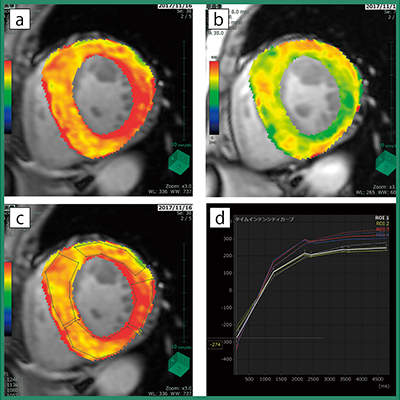

今回,最新のバージョンでは,心筋領域に対しピクセルごとにT1値を計算する“心筋TxMap”アプリケーションをリリースした(図1)。Modified Look-Locker Inversion Recovery(MOLLI)法で収集されたMR画像からおのおののT1値を算出する。一般的にT1 Mappingには2種類のパラメータが存在し,造影前MR画像からT1値を計算したものをNativeT1Map,造影後MR画像から計算したものをT1Mapと呼ぶ。基本的には造影前後のMR画像を用いることが多いが,造影剤投与が禁忌なケースも考慮し,非造影MR画像のみからT1値を計算できるようになっている。

図1 心筋TxMapの解析結果画像例

a:NativeT1Map(表示範囲0〜1500ms)

b:T1Map(表示範囲0〜800ms)

c:ROI設置例

d:設定した各ROIのタイムインテンシティカーブ(実線:実測値を直線で結んだ線,点線:実測値を基に計算した近似曲線)